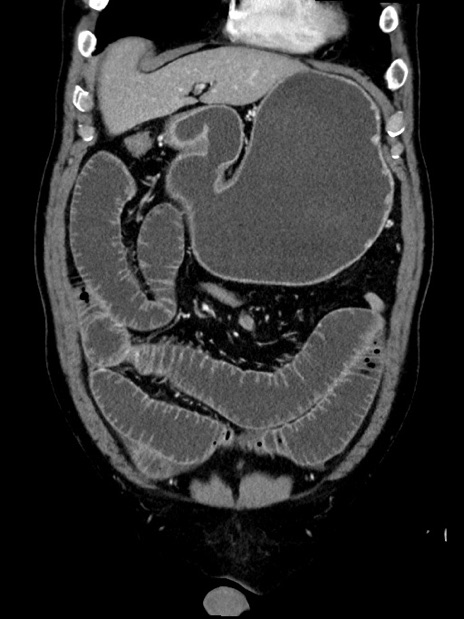

症例35(冠状断像)

症例

【症例】70歳代 男性

【主訴】腹部膨満、嘔吐

【現病歴】昨日より腹部膨満感出現。本日増悪し、仙痛出現。嘔吐あり、受診。

【既往歴】糖尿病、胆摘後

【身体所見】BP 149/80mmHg、HR 74/min、BT 35.9℃、腹部:膨満、軟、圧痛なし。腸雑音減弱あり。上腹部正中切開瘢痕あり。

【データ】WBC 13500、CRP 1.72